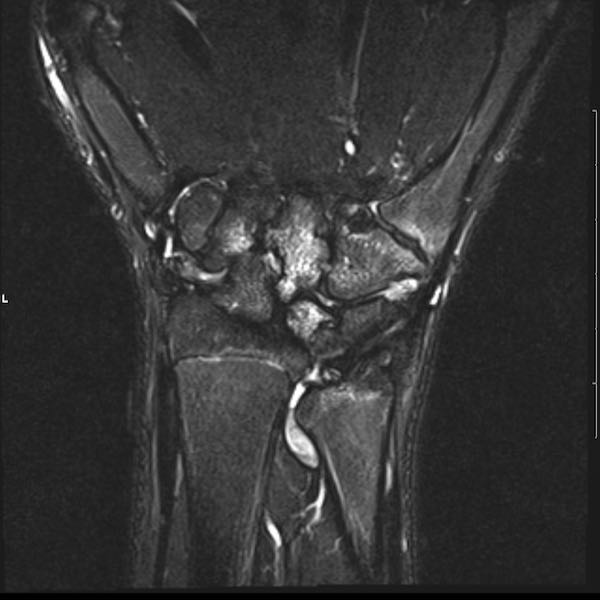

Tiếp tục xem hình ảnh MRI của bệnh nhân này.

Hình ảnh MRI:

Tràn dịch lan tỏa tất cả các khớp cổ tay.

Phù tủy xương lan tỏa tất cả các xương cổ tay.

Bào mòn xương, ví dụ tại xương thuyền, xương đầu và xương móc.

Phá hủy khe khớp và sụn khớp, rõ nhất tại khớp STT và CMC4/5.